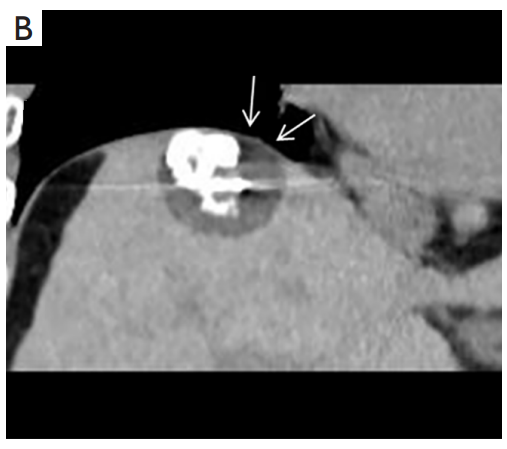

背景:由于一些原因,位于膈肌附近的腫瘤的熱消融在技術(shù)上具有挑戰(zhàn)性。首先,術(shù)中計算機掃描和超聲檢查無法清晰顯示射頻消融/微波消融切緣。第二,消融過程中不利的針分布和過熱可能導致肝包膜破裂,并對膈、肺和心臟造成嚴重損傷。第三,即使使用人工腹水,仍有9~22%的患者因肝周粘連或腫瘤位置靠近肝表面而導致膈肌熱損傷。冷凍消融可能是毗鄰膈肌的HCC的一種有前途的治療方法,因為在消融過程中使用CT和US可以很好地顯示腫瘤邊緣。盡管一些研究評估了在高危區(qū)域使用冷凍消融治療HCC,但很少有研究針對膈肌臨近區(qū)域。

背景:肝癌是中國最常見的惡性腫瘤之一,發(fā)病率和死亡率都很高。雖然手術(shù)切除是最好的治療方法,但大多數(shù)患者處于晚期或直到住院才有手術(shù)指征。對于單個腫瘤直徑小于5厘米的患者,微創(chuàng)治療與手術(shù)切除效果相當;多個病灶小于3個,單個病灶最大直徑小于3cm;不侵犯血管、膽管、鄰近器官和遠處轉(zhuǎn)移。雖然一些傳統(tǒng)消融技術(shù)方式可以使部分患者受益,但不適用于特殊部位肝癌(定義為毗鄰大血管、肝外臟器和重要結(jié)構(gòu)的腫瘤)的治療。冷凍消融作為一種相對較新的治療方式,具有明顯的冰球效果、療效好、激活抗腫瘤免疫、并發(fā)癥發(fā)生率低等優(yōu)點,尤其適用于特殊部位肝癌患者的治療。我們的研究目的是探討CA治療特殊部位肝癌的安全性、可行性和有效性。